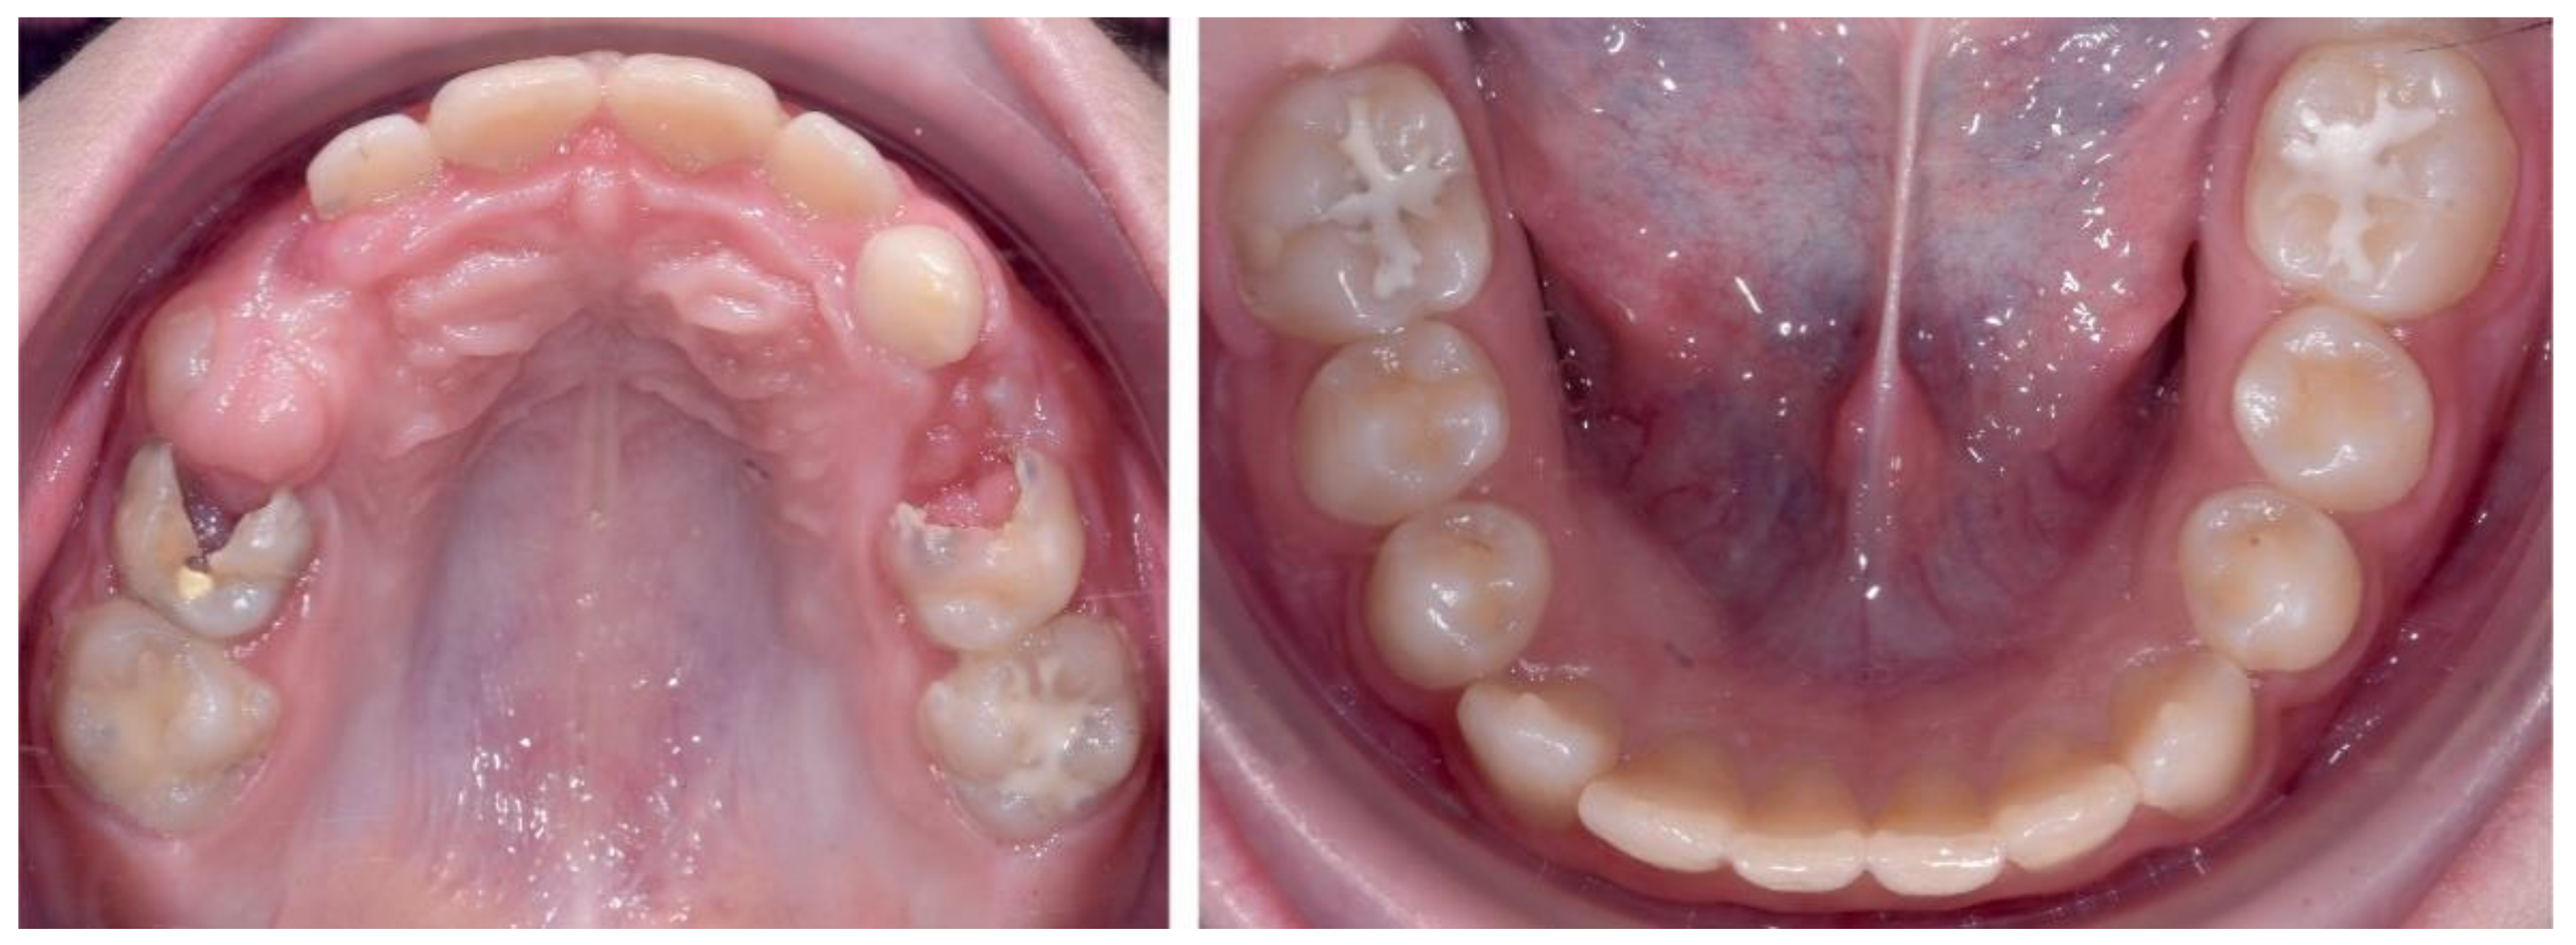

2.2.1. Initial Examination

2.3.2. Second Phase of Treatment—2017—Bite-Blocks and Transpalatal Arch